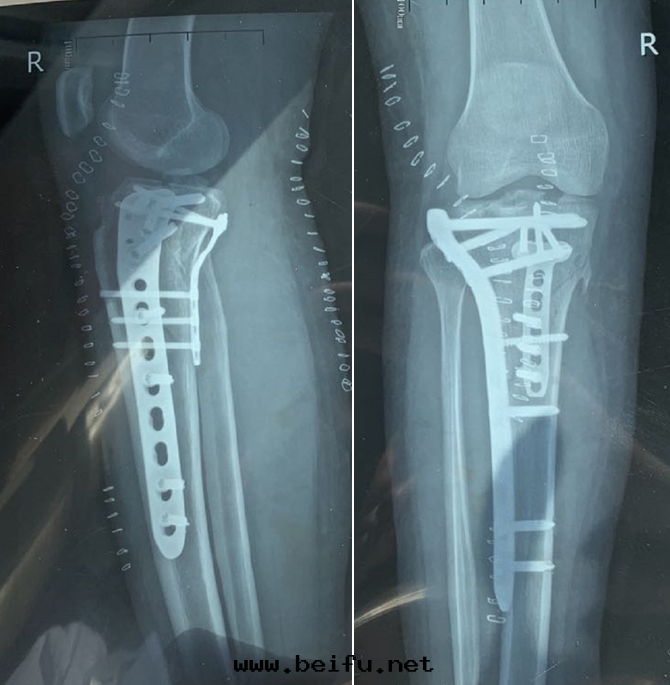

核磁檢查後(hòu),C女士在(zài)玉(yù)門(mén)市(shì)中醫醫院(yuàn)接受了(le)“右(yòu)胫骨(gǔ)骨(gǔ)折內(nèi)固定(dìng)手(shǒu)術(shù)”治療,並(bìng)行“交叉(chā)韌带(dài)重(zhòng)建手(shǒu)術(shù)”治療。

▲患者(zhě)影像学檢查